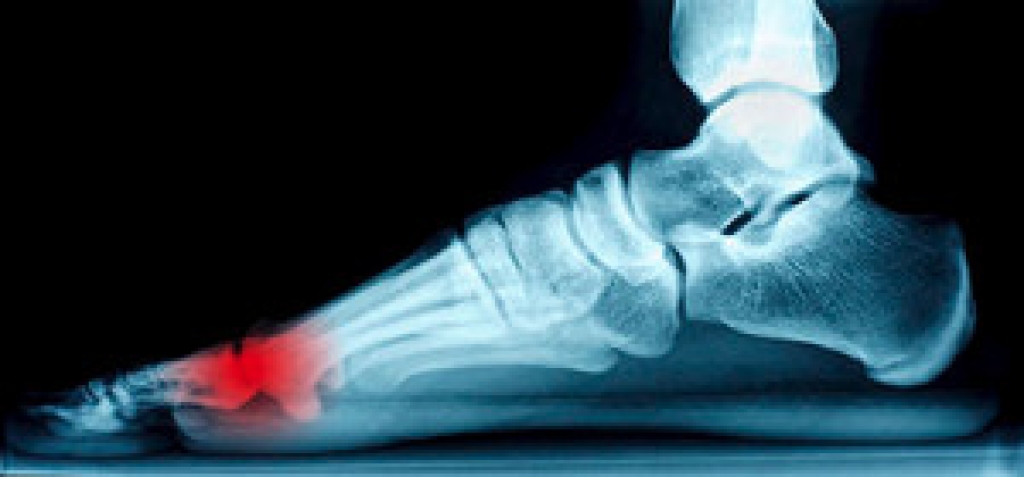

Heel spurs are formed by calcium deposits on the back of the foot where the heel is. This can also be caused by small fragments of bone breaking off one section of the foot, attaching onto the back of the foot. Heel spurs can also be bone growth on the back of the foot and may grow in the direction of the arch of the foot.

Older individuals usually suffer from heel spurs and pain sometimes intensifies with age. One of the main condition's spurs are related to is plantar fasciitis.